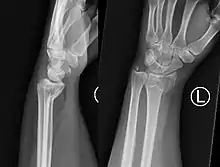

Fratura de Smith

Uma fratura de Smith, também conhecida como fratura de Colles invertida é uma fratura do rádio distal causada por queda sobre punhos fletidos, ao contrário da fratura de Colles, que ocorre em queda sobre punho estendido.